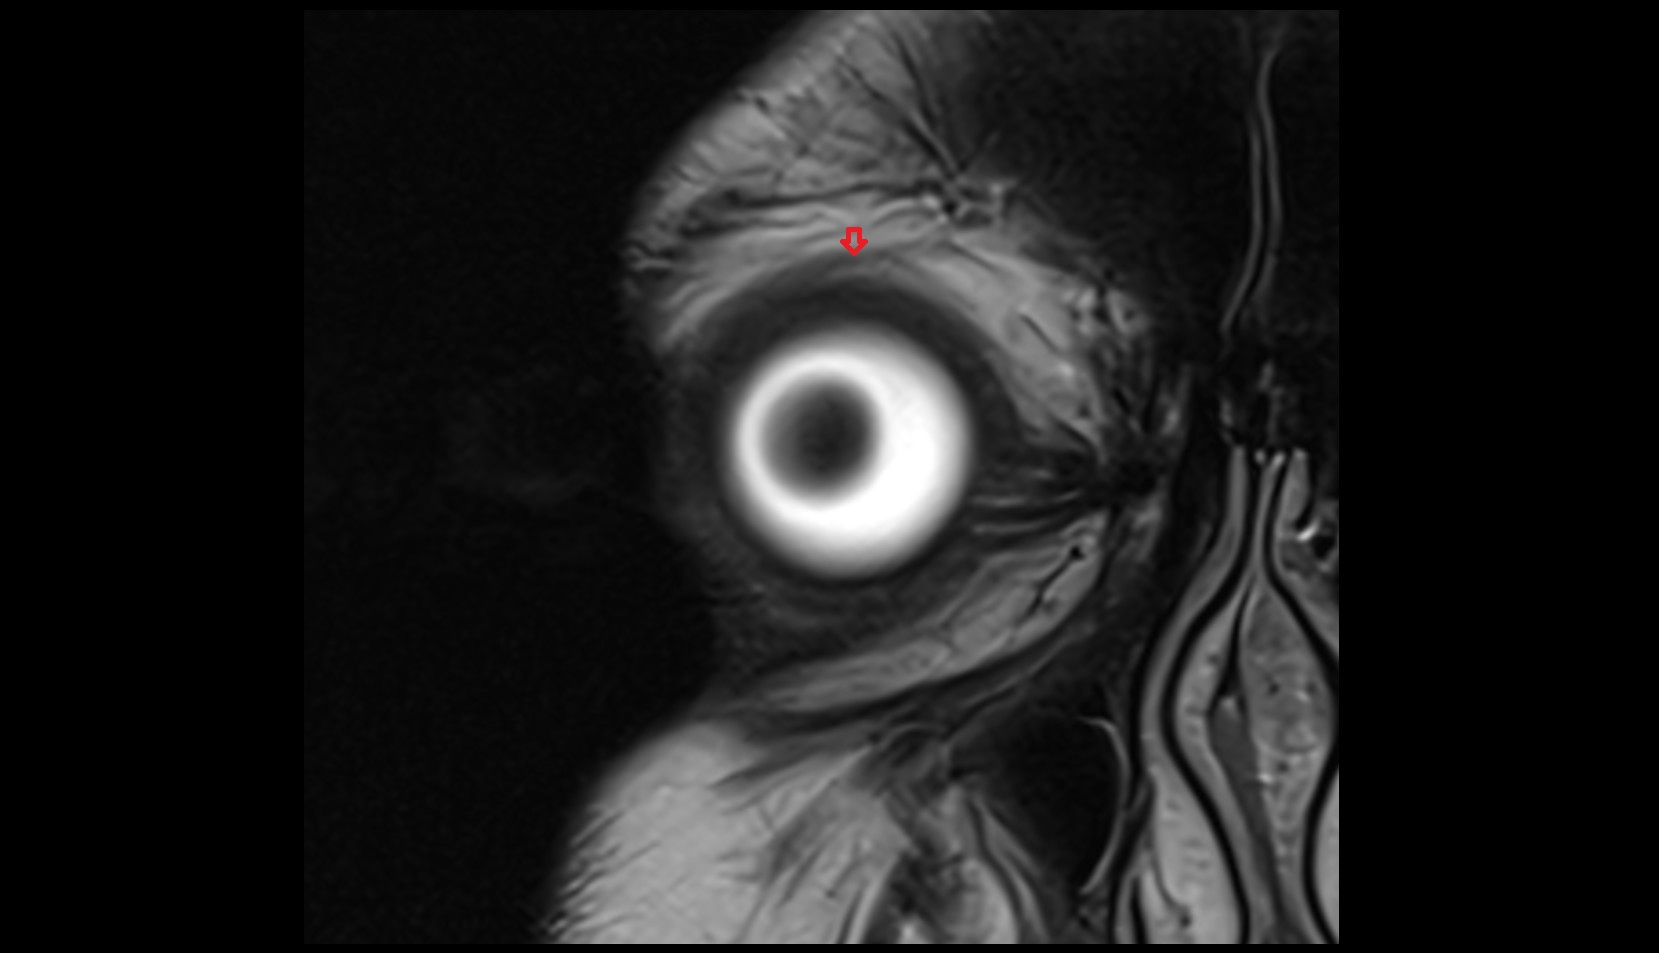

- Orbital part of optic nerve

- Optic nerve sheath

- Subarachnoid space of optic nerve

- lens of the eye

- Cornea

- Iris

- Pupil

- Anterior chamber of eyeball

- Posterior chamber of eyeball

- Vitreous chamber of eyeball

- Sclera

- Choroid

- Retina

- Optic disc